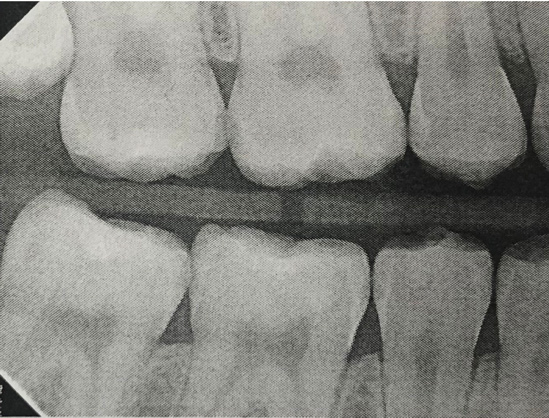

Fig 12. Six-month results of SDF proximal surface saturation in a teenaged patient. As seen in pretreatment bitewing film (Fig 12) and 6-month post-SDF bitewing films (Fig 13 and Fig 14), proximal radiolucencies appeared unchanged while some improved.

Fig 13. Six-month results of SDF proximal surface saturation in a teenaged patient. As seen in pretreatment bitewing film (Fig 12) and 6-month post-SDF bitewing films (Fig 13 and Fig 14), proximal radiolucencies appeared unchanged while some improved.

Figure 13

The senior author's (TPC) private practice experience with soft-tip insertion of SDF into contacting proximal surfaces of teeth is that most beginning proximal surface caries lesions cease to progress, as evidenced by subsequent bitewing radiographic comparisons (Figure 3 through Figure 6, Figure 12 through Figure 18). The chances for success vary, however, depending on frequency of application, subsequent flossing by patients or adults flossing younger children, diet control, individual mouth chemistries, and use of fluorides for the topical effect. It must also be emphasized that office staff should make extensive efforts to inform children and parents that subsequent daily flossing is needed to accompany SDF treatments; otherwise, SDF applications will only delay the inevitable progression of caries. Flossing methods should be demonstrated for patients and for parents so they may see how to floss younger children. Showing them enlarged graphic photographs of flossing results may be helpful in this regard. Parents and patients should be made aware that if interproximal dental plaque accumulations persist without daily interruption by flossing, the acid insult will eventually take its toll on the proximal surfaces and caries lesions will progress to the point where restorative intervention may be required.